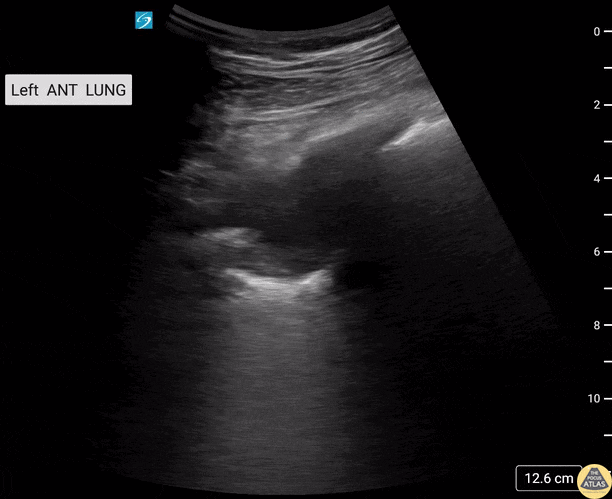

HIV+ male patient presents with cough and shortness of breath. Thoracic US demonstrated a left upper lobe cavitary lesion with calcifications. Differentials included TB, aspergilloma, lung abscess. Contributors: Sara Schambach, MD; Garrett Mason, MD